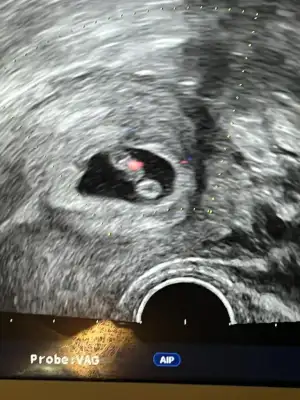

Kızlar bu arada cinsiyet tahmini yapabilen var mı aranız da

Genel de tutuyor tahminlerim şansımı denerim ultrason resmini gönderirsen

Bunlar yakından foto uzaktan altta olan kısım yok gibi görünüşe göre erkeğe benziyor tabi bu kese durumuna bakarak tahmin ediyorum.Nub teorisi için de -12. Haftalarda gidersen ona göre de yorum yaparım.Allah gönlünde kini saglikcakla.nasip.etsin inşallahBi bak canım

Nasıl kız. Kesenin şekline göre belli oluyor mu Ayy bende merak ettimBunlar yakından foto uzaktan altta olan kısım yok gibi görünüşe göre erkeğe benziyor tabi bu kese durumuna bakarak tahmin ediyorum.Nub teorisi için de -12. Haftalarda gidersen ona göre de yorum yaparım.Allah gönlünde kini saglikcakla.nasip.etsin inşallah![]()